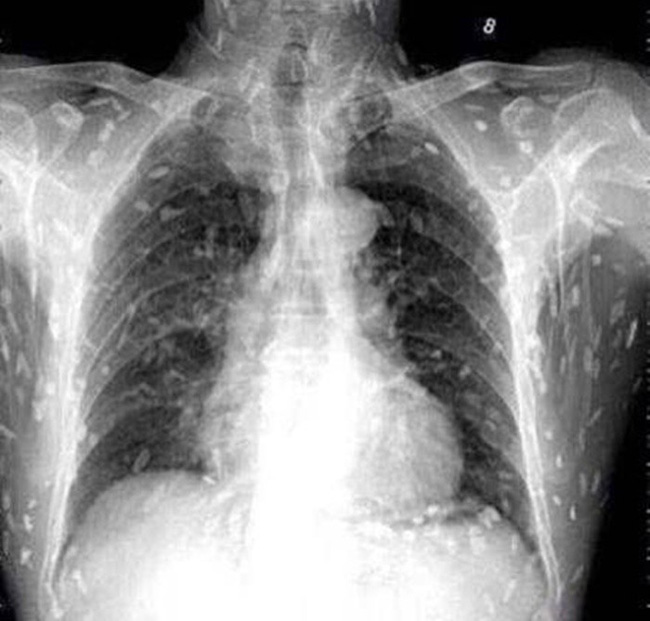

Tuy nhiên, do bệnh tình đã bước sang giai đoạn nghiêm trọng nên người đàn ông tiếp tục được chuyển tới Bệnh viện Nhân dân số 8 ở Quảng Châu để điều trị. Kết quả chụp X-quang cho thấy, những đốm trắng nhỏ xuất hiện lấm chấm khắp cơ thể chính là sán.